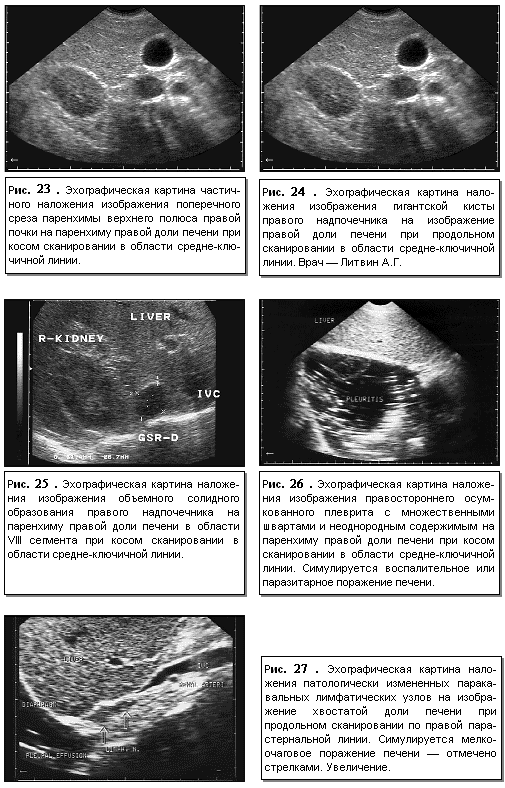

Определенное влияние на качество и характер изображения печени может оказывать наложение изображения прилегающих органов и структур и патологических процессов в них (рис. 23-27).